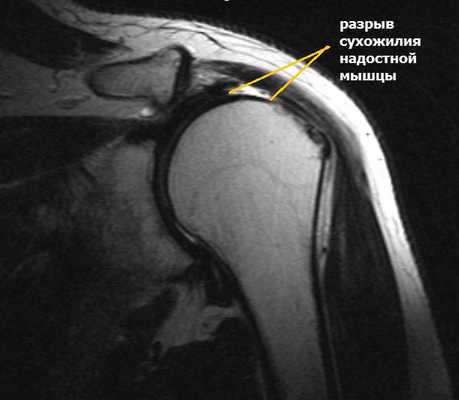

- адекватная предоперационная диагностика (предпочтение отдают МРТ);

Перед артроскопией оценивается длина и ширина разрывов, степень жировой дистрофии мышц, протяженность и локализация травмы. При наличии признаков значительного жирового перерождения мышечной части манжеты в сочетании с некрозом головки плечевой кости артроскопическая операция не поможет. В таком случае рекомендовано эндопротезирование плечевого сустава.

Сужение пространства между акромионом и головкой плечевой кости (импинджмент-синдром) возникает на фоне особого строения акромиального отростка или после получения травмы. Сухожилие надостной мышцы, проходящее в данном пространстве, попадает как бы в тиски и постепенно сдавливается.